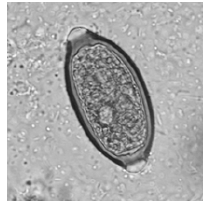

Durante um exame parasitológico de fezes você avistou a seguinte estrutura:

Fonte: Atlas de parasitologia clínica - www. parasitologiaclinica.ufsc.br

Ao reportar o laudo, você deve afirmar a presença de ovos de qual parasita?